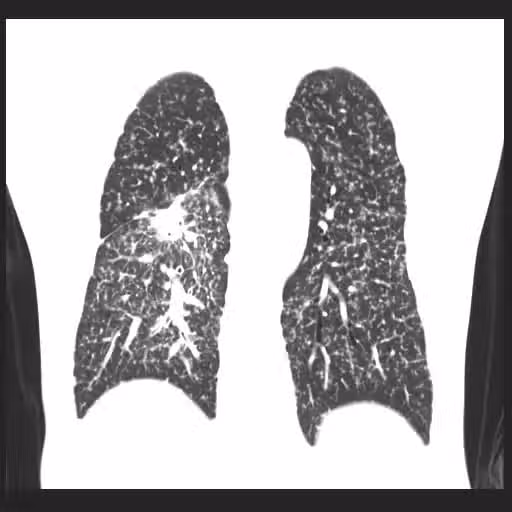

媽媽、2個兒子全肺癌!他一查末期... 醫嘆「用這清潔劑」等於抽20支煙 #3電器也上榜

他建議,病患家屬最好在親人「診斷出肺癌的年齡提前10歲」做篩檢,目前最有效的檢測方式是「低劑量電腦斷層」篩檢,如果肺部乾淨沒有結節,那麼往後3至5年都算安全。另外,蘇一峰也提醒,想要遠離致癌因子,除了油煙、二手煙、空污外,使用家中電器、公司印表機時,也要特別注意...